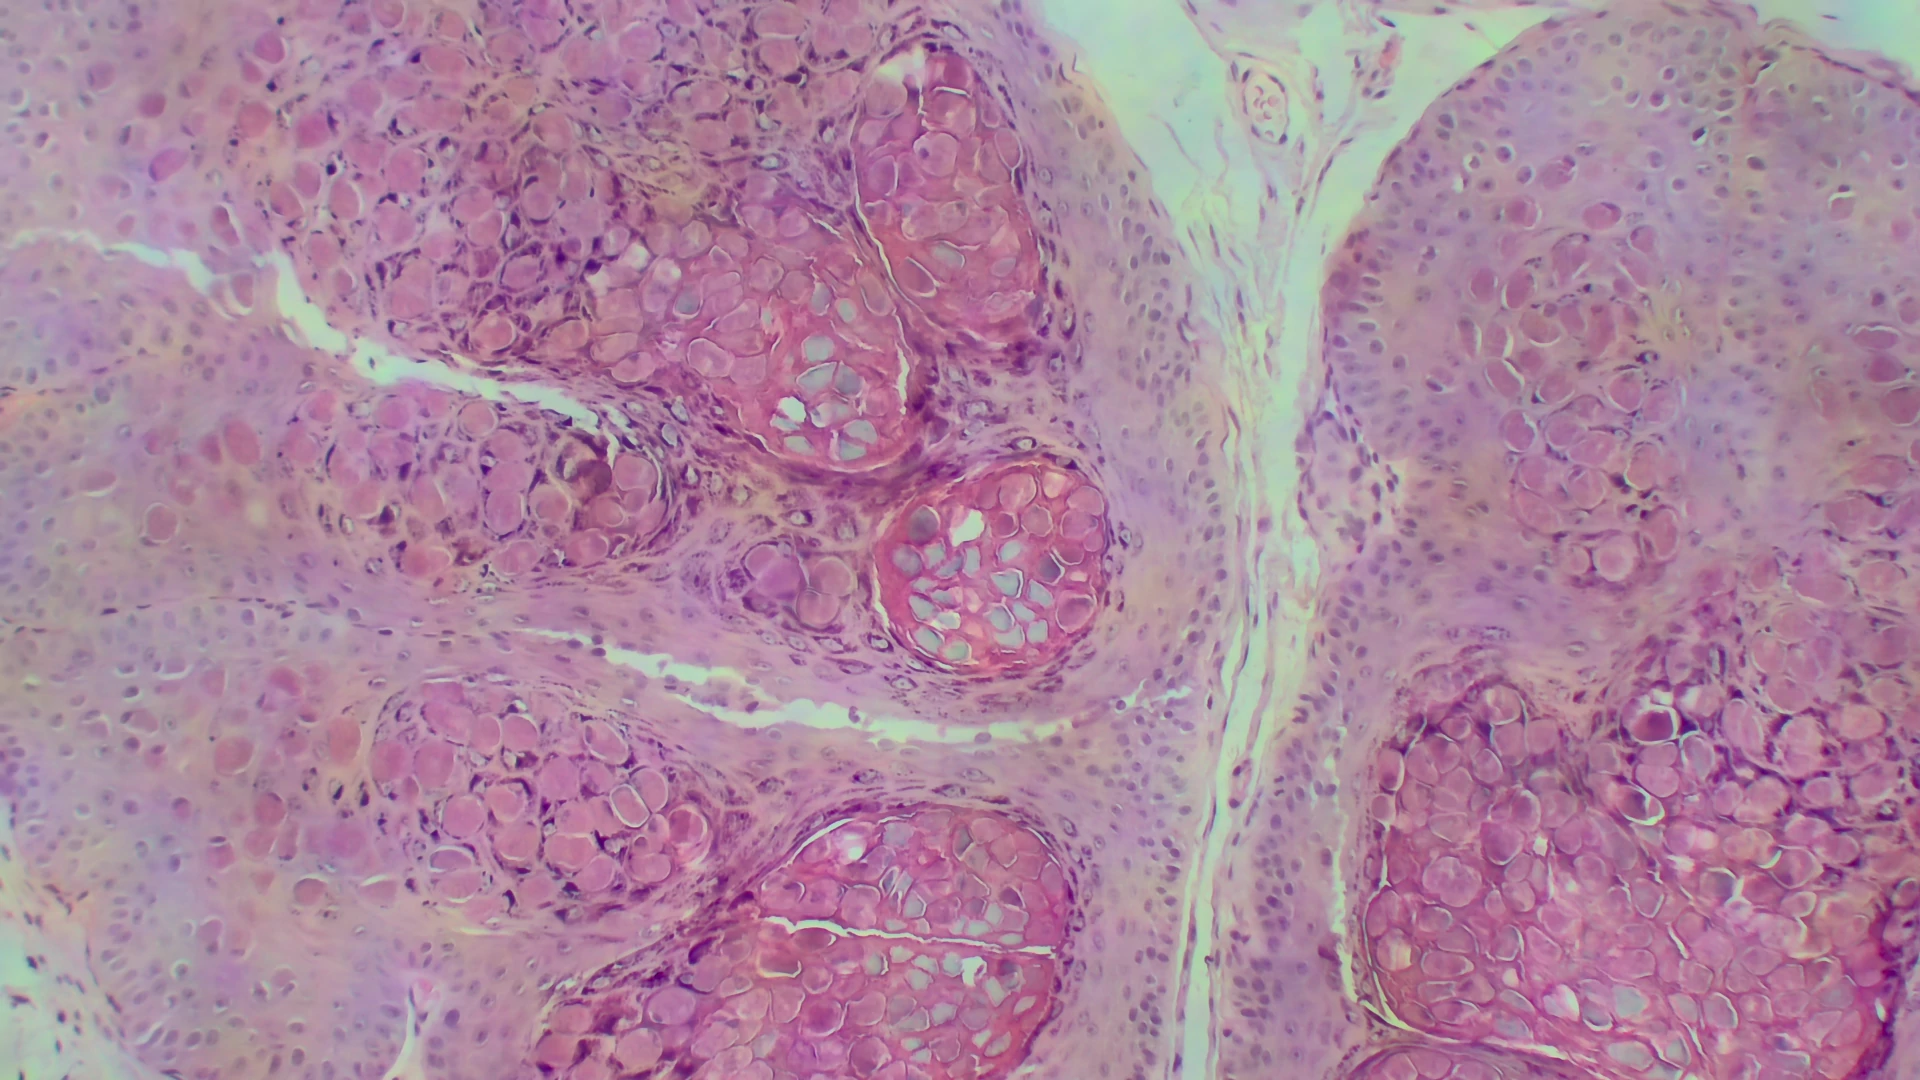

Intestine, HE staining, brightfield contrast